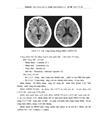

1.8.3. Chụp CLVT tưới máu não

3.2. Hình ảnh chụp cắt lớp vi tính và cộng hưởng từ

3.3. Vai trò của chụp cắt lớp vi tính tưới máu não